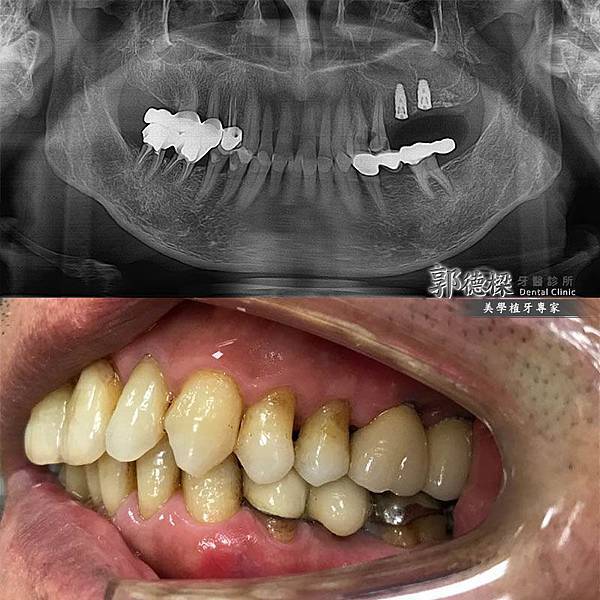

長年口腔清潔不確實,嚴重牙周病狀缺牙,透過...

36歲嚴重缺牙、掉牙,人工植牙搭配假牙牙橋恢...